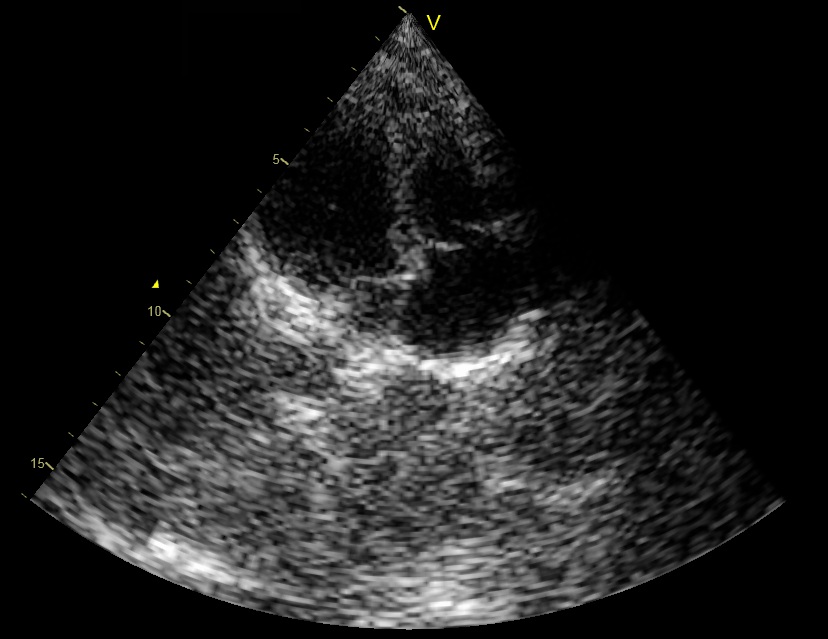

To demonstrate the equivalence of beamforming in time and frequency, we applied both methods on in vivo cardiac data yielding the images shown in Fig. 3. The imaging setup is that described in Section II-B with MHz. As can be readily seen, the images look identical.

The resulting images, corresponding to two different frames, are shown in Figs. 7f (b) and (e). Although the images are not identical to those obtained by standard beamforming (Figs. 7f (a) and (d)), it can be easily seen that optimization, based on the assumption that the signal of interest is compressible, allows to reconstruct both strong reflectors and speckle. Table II reports corresponding values of NRMSE and SSIM. Although the quantitative values are reduced compared to those obtained in Sec. IV-B, important information, e.g. the thickness of the heart wall and the valves, as well as the speckle pattern, essential for tracking tools, are preserved.

Using this set, beamforming in frequency was performed according to (16) and (20), yielding the DFT coefficients of the beamformed signal. In this setup the sampling rate remained unchanged, but frequency domain beamforming was performed at a low rate. In our experiments we computed DFT coefficients of the beamformed signal, using DFT coefficients of each one of the detected signals. This corresponds to real-valued samples used for beamforming in frequency. The number of samples required by demodulated processing rate is . Hence, beamforming in frequency is performed at a rate corresponding to of the demodulated processing rate. Images obtained by low-rate beamforming in frequency and standard time-domain beamforming are presented in Fig. 11. As can be readily seen, we are able to retain sufficient image quality despite the significant reduction in processing rate.